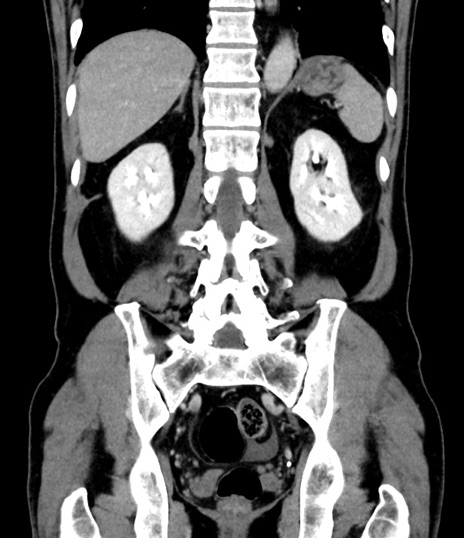

症例8(冠状断像)

【症例】 60歳代男性

【主訴】 黒色吐物

【現病歴】 4日前から嘔気自覚、2日前の朝食後にも嘔気あり、自分で手で嘔吐反射起こし嘔吐したところ血が混ざっていたため受診。

【既往歴】 5年前汎発性腹膜炎を伴う急性虫垂炎で手術、高血圧、前立腺肥大症、高脂血症

【身体所見】 腹部正中に手術癩痕あり 腹部平坦・軟圧痛なし膨満感あり

【データ】WBC 8400、CRP 4.54